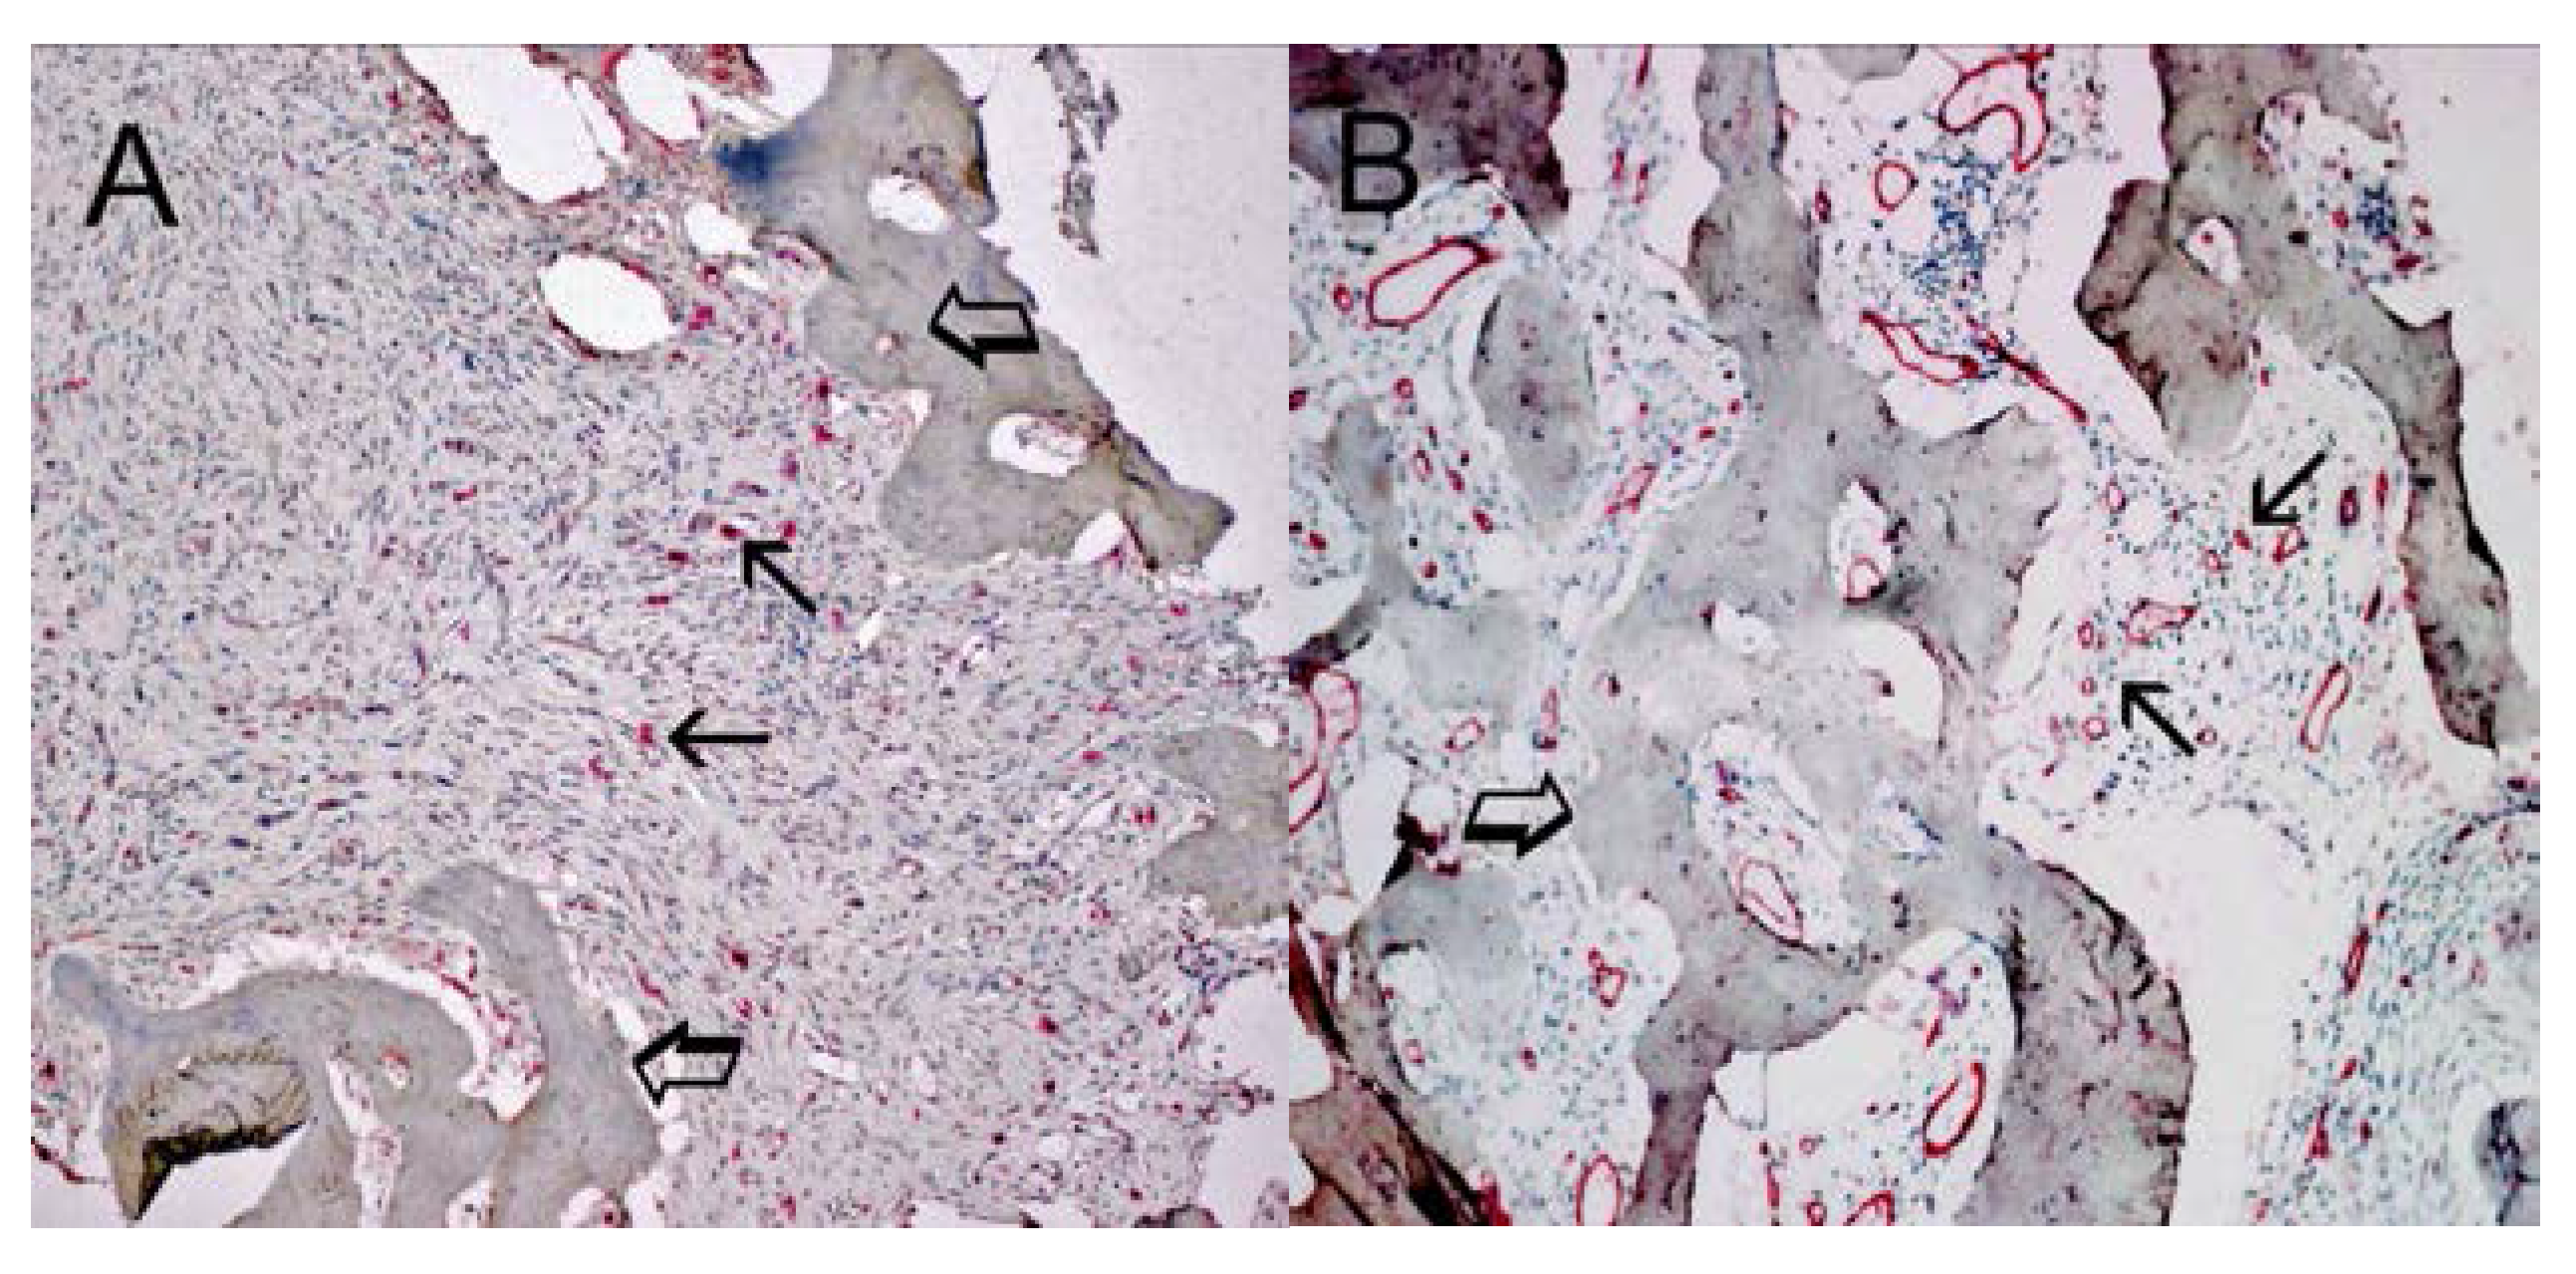

Infiltrating Mast Cells Correlate with Angiogenesis in Bone Metastases from Gastric Cancer Patients

2. Results

3. Discussion